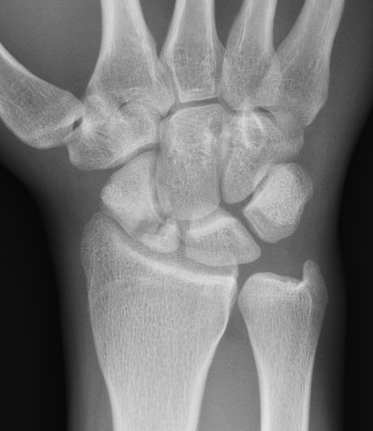

Xray

Nonunion with minimal displacement and minimal resorption

Nonunion with significant displacement and bone resorption

Proximal pole fracture with displacement and absorption